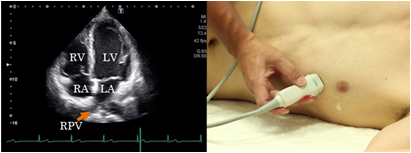

Apical 4 chamber view

The apical 4 chamber view is found by placing the probe at the apex located at the apical impulse. The left chambers are seen on the right of the screen and the right chambers on the left of the screen. Fix the image when the 4 chambers look the largest. The important point is to visualize the left ventricular apex directly under the probe on the screen. This view is suitable for evaluation of 4 chamber balance and wall motion abnormalities and abnormalities of the attachment site of atrioventricular valves. It is also suitable for the measurement of left ventricular volume, left ventricular ejection rate, and for recording of pulmonary venous blood flow patterns.